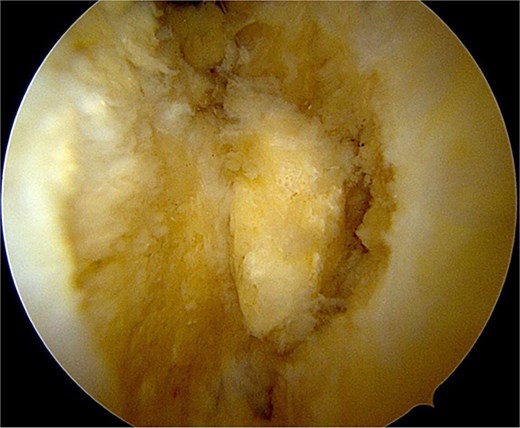

Once the ossicle was mobile and free (Fig. 6), it was removed either in one piece or was broken into multiple pieces with an arthroscopic burr and then removed with a grasper (Figs 7 and 8). Finally, the tibial tubercle was leveled using either an arthroscopic burr or shaver.

Arthroscopic views of case 1. (A) Ossicle fragment removed. Case 2 (B) tibial tubercle leveling using an arthroscopic Burr. Case 3 (C) ossicle fragment removed.

Complete excision was confirmed intraoperatively with fluoroscopy. Hemostasis was achieved by coagulating small synovial vessels, and the procedure was concluded with portal closure.